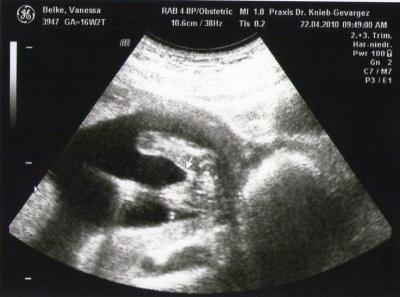

Huhu Süße!! hatte heute mal wieder Fa-termin.Alles Bestens allerdings hab ich ne Vorderwandplazenta ,was ja nicht weiter tragisch ist :-) Und ein Outing :-) Und was meinst du ;-) Wie gehts die den so?? LG Nessi

Bild zu @dawn (outing) - Forum für November - Mamis

heyyy!! schön, dass alles in ordnung ist!!! das bild sieht interessant aus! da ich keinen ziepel erkennen kann, würde ich sagen mädchen?? *neugierig*

Ja Mädchen laut Fa...hast du noch nen Outing Foto von deiner Tochter!!!Ja hier ist das foto ganz schön klein..mal sehen ob ich es größer bekomme...